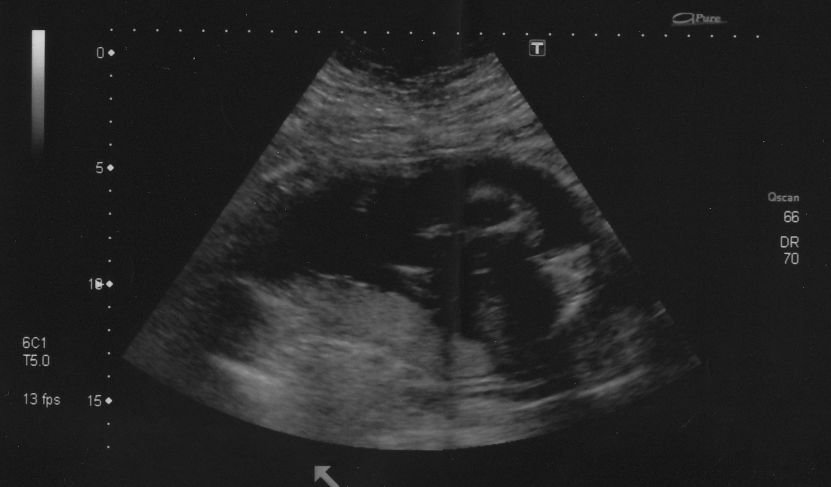

Danyoo wrote:The technician was having a hard time getting measurements because Cody was so active. "If I could just get baby to stop moving for a tenth of a second...I could measure his femur!"